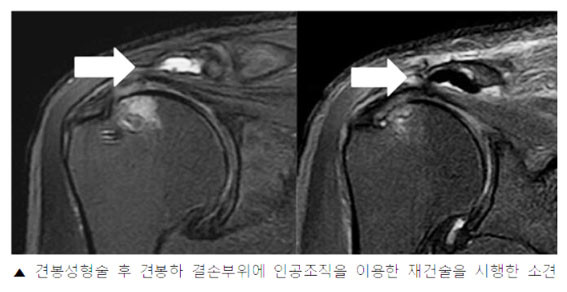

À̹ø ¿¬±¸¿¡¼ À¯À缺±³¼ö´Â ¾î±ú ȸÀü±Ù°³ ÁõÈıº¿¡¼ ½ÇÆÐÇÑ °ßºÀ¼ºÇü¼ú·Î ÀÎÇØ ¹ß»ýÇÏ´Â Áö¼ÓÀûÀÎ ÅëÁõ ¹× Ãæµ¹ Áõ»óÀ» ÇØ°áÇϱâ À§ÇÑ Ä¡·á¹ýÀ¸·Î½á ÀΰøÁ¶Á÷À» ÀÌ¿ëÇÑ °ßºÀ Á¡¾×³¶ Àç°Ç¼úÀ» ½ÃÇàÇÏ¿© Áõ»óÀÌ È£ÀüµÇ´Â °á°ú°¡ ³ªÅ¸³µÀ½À» È®ÀÎÇß´Ù.

| | ¡è¡è <»çÁøÁ¦°ø=õ¾È¾Æ»êÃæ¹«º´¿ø> | ¨Ï ¿Â¾ç½Å¹® | | À¯À缺 ±³¼ö´Â ¡°À̹ø ¿¬±¸¸¦ ÅëÇØ ¾î±ú ȸÀü±Ù°³ ÁõÈıºÀ¸·Î °íÅë ¹Þ´Â È¯Àڵ鿡°Ô º¸´Ù ´õ È¿°úÀûÀÎ Ä¡·á¸¦ Á¦°øÇÒ ¼ö ÀÖÀ» °ÍÀ¸·Î ±â´ëµÈ´Ù´Â Á¡¿¡¼ À¯ÀǹÌÇÑ ¿¬±¸¿´´Ù°í »ý°¢ÇÑ´Ù. ¾ÕÀ¸·Îµµ ȯÀڵ鿡°Ô ÃÖ¼±ÀÇ Áø·á¸¦ Á¦°øÇÔÀº ¹°·ÐÀ̰í, ½ÇÁúÀûÀÎ µµ¿òÀ» µå¸± ¼ö ÀÖ´Â Ä¡·á¹ý ¿¬±¸ ¹× °³¹ß¿¡µµ Èû¾²°Ú´Ù.¡°°í ÀüÇß´Ù.